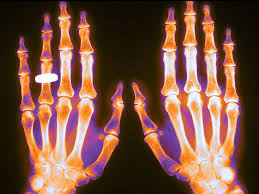

Las dosis de glucocorticoides tan bajas como 2,5 mg/día se asociaron con la pérdida de densidad mineral ósea (DMO) en pacientes con enfermedades musculoesqueléticas reumáticas inflamatorias (EMRi), pero este efecto se pudo prevenir. La pérdida de DMO en pacientes que recibieron ≥5 mg/día no se previno por completo con los medicamentos contra la osteoporosis que se usan actualmente en la práctica clínica, lo que resultó en un mayor riesgo de fractura. Arthritis Rheumatol, 24 de abril de 2023